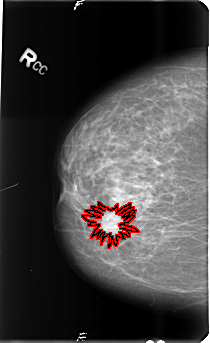

B_3488_1.RIGHT_CC

FILE: B_3488_1.RIGHT_CC.OVERLAY

TOTAL_ABNORMALITIES 1

ABNORMALITY 1

LESION_TYPE MASS SHAPE IRREGULAR-ARCHITECTURAL_DISTORTION MARGINS SPICULATED

ASSESSMENT 5

SUBTLETY 5

PATHOLOGY BENIGN

TOTAL_OUTLINES 1

BOUNDARY